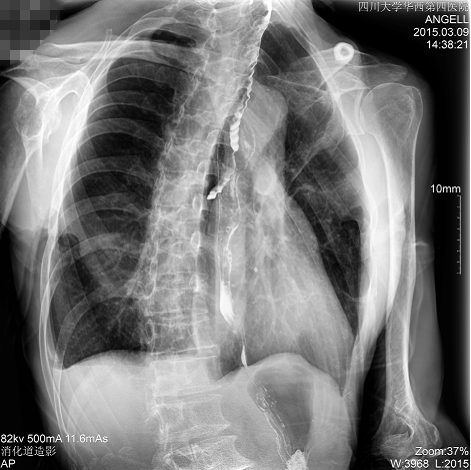

如下圖所示:該患者因吞咽時(shí)感到很難受,進(jìn)食時(shí)也經(jīng)??人怨示歪t(yī)診斷。使用多功能dr為病人進(jìn)行消化道造影診斷,要求他吞鋇后發(fā)現(xiàn),食道各段通過(guò)順利,形態(tài)規(guī)則,雙側(cè)梨狀窩不對(duì)稱左側(cè)稍淺,多次吞咽動(dòng)作后,仍見(jiàn)鋇劑滯留,并見(jiàn)鋇劑進(jìn)入氣管,屬于會(huì)厭征陽(yáng)性。會(huì)厭功能紊亂,鋇劑進(jìn)入了氣管。

圖為正位:通過(guò)動(dòng)態(tài)影像可以清楚看到鋇劑進(jìn)入了支氣管道且雙側(cè)梨狀窩不對(duì)稱

圖為斜位:通過(guò)動(dòng)態(tài)影像可以清楚看到鋇劑進(jìn)入了支氣管道

通過(guò)多功能dr可以診斷該病人的癥狀為會(huì)厭功能紊亂,鋇劑進(jìn)入到了氣管。而在動(dòng)態(tài)透視下可以清晰的觀察到鋇劑從何處進(jìn)入氣管,可清晰顯示食管粘膜結(jié)構(gòu)。使用多功能dr其獨(dú)特的視頻采集技術(shù),可實(shí)時(shí)保存視頻并能實(shí)現(xiàn)900萬(wàn)像素實(shí)時(shí)點(diǎn)片,才能獲取這樣清晰的病灶點(diǎn)。而常規(guī)dr只能拍攝靜態(tài)片,且成像效果大打折扣,因此較難確診病灶。